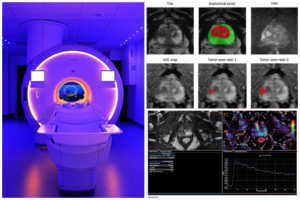

Πολυπαραμετρική Μαγνητική Τομογραφία

Το νέο αυτό διαγνωστικό εργαλείο αποτελεί σήμερα την ακριβέστερη απεικονιστική  μέθοδο για την ανίχνευση πιθανών ύποπτων περιοχών-βλαβών  για τον καρκίνο του προστάτη και  τη σταδιοποίηση του .

Η διάγνωση βασίζεται σε πεντα-βάθμιο (1-5) σύστημα ταξινόμησης  PI-RADS των περιοχών του προστάτη που χαρτογραφούνται και  η οποία συνήθως καθορίζει την διενέργεια ή μη βιοψίας κατευθυνόμενης στη βλάβη (targeted-fusion)